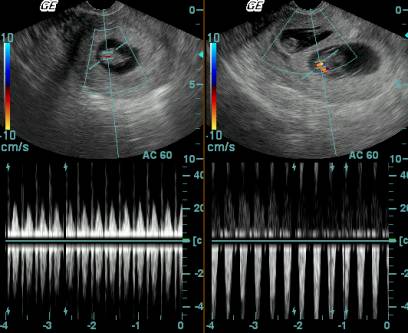

A repeat Transvaginal sonography was done with needle guide on it by center’s gynecologist . The closest sac was focused. A needle from Reproline 35 cm and 17 g was introduce into the thorax of the fetus and 2 ml of KCL (2 meqv/ml) injected into the thorax of the fetus .There was instant asystole .The cardiac activity of all the fetus was confirmed by simultaneous color Doppler .

Next day on 21st October 2006 ,repeat sonography was done to confirm the fetal death. Other fetuses were normal and there was no bleeding